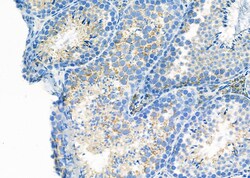

| Applications | Immunohistochemistry (Paraffin), Western Blot, Immunocytochemistry |